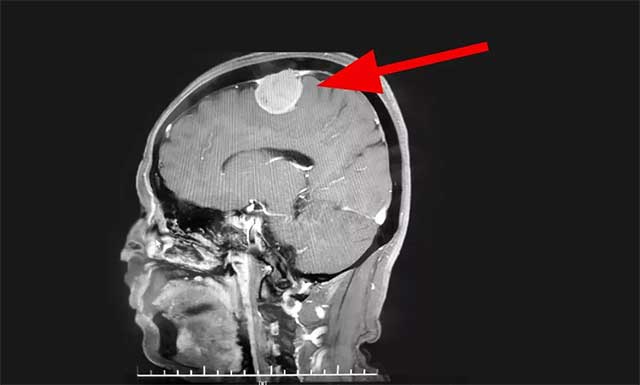

▲ 患者術(shù)前磁共振影像

醫(yī)院神經(jīng)外科主任沈建康教授、神經(jīng)外科6A病區(qū)侯增欣主任團隊在對患者完善相關(guān)檢查,并開展嚴謹?shù)姆治鲈u估后認為:趙女士的腫瘤位于腦部重要功能區(qū)——中央前回附近,體積較大,占位效應明顯,患者手術(shù)指征明確。在明確告知患者及家屬手術(shù)風險并簽字確認后,由沈建康教授主刀,為趙女士行腫瘤切除手術(shù)。

術(shù)中可見,患者硬腦膜局部凸起,有明顯腫瘤侵犯,硬膜動脈增粗。切開硬膜后,乒乓球大小(約4CM*4CM)的腫瘤呈灰白色,血運豐富。沈建康教授取瘤組織標本病理送檢后,開始著手分塊切除腫瘤。

在顯微鏡下,腫瘤自矢狀竇向外生長,瘤體已包裹住了一支較大的皮層引流靜脈。這條靜脈非常重要,負責引流中央腦回的血流,必須完整保留。一旦損傷會引起靜脈性水腫,嚴重的可導致災難性后果——患者偏癱甚至死亡。